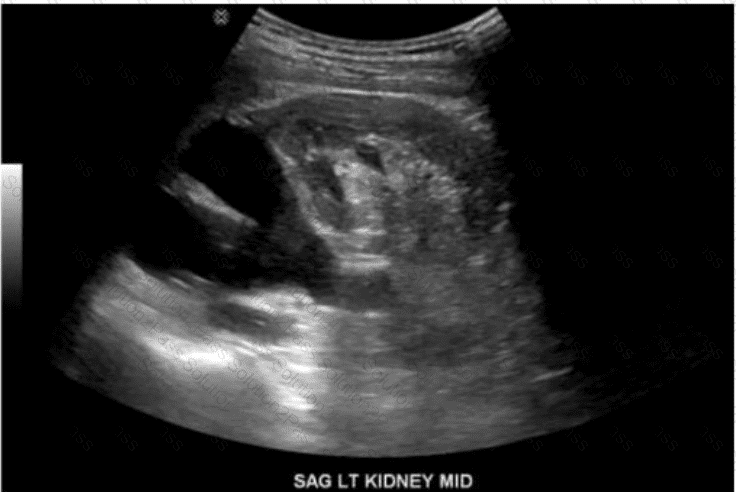

Which congenital anomaly is demonstrated in this image?